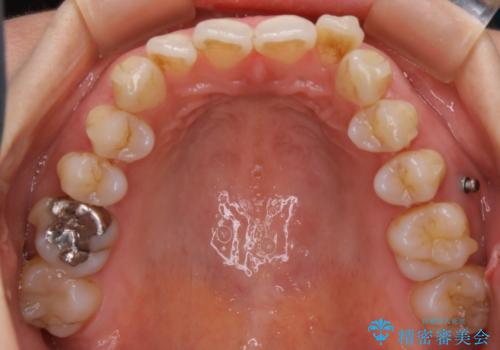

ガタつき自体は歯列の幅の拡大やディスキング(IPR)でほとんど解消可能でしたが、噛み合わせのズレは歯の移動が必要だったため、左上にマイクロインプラントを使用し噛み合わせの改善とガタつきの解消を同時に進めるという方針をとりました。

ディスキング(IPR)

歯のガタつきをとるためのスペース作りの方法の一つにディスキング(IPR)という方法があります。

歯と歯の間を一ケ所あたり最大0.5mmまでの範囲内で削ることで歯自体が少し小さくなり、それにより作られるスペースを数ヶ所分合わせることで合計で数mmの大きなスペースが作れるという方法です。

当院ではなるべく歯の機能や見た目に影響の出ないよう、作業時に拡大鏡の使用や削るタイミングの微調整を行っています。